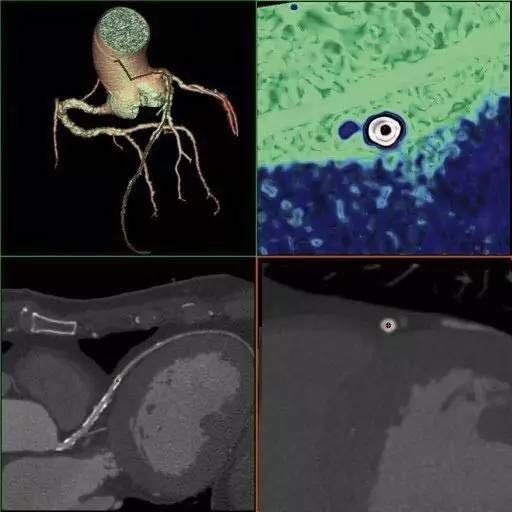

CardIQ Xpress 2.0 Reveal

至简的工作流程,一键式2D/3D冠脉重建,轻松测量管腔狭窄、斑块密度、斑块长度。一键式心功能计算......CardIQ Xpress 2.0 Reveal足够出色。